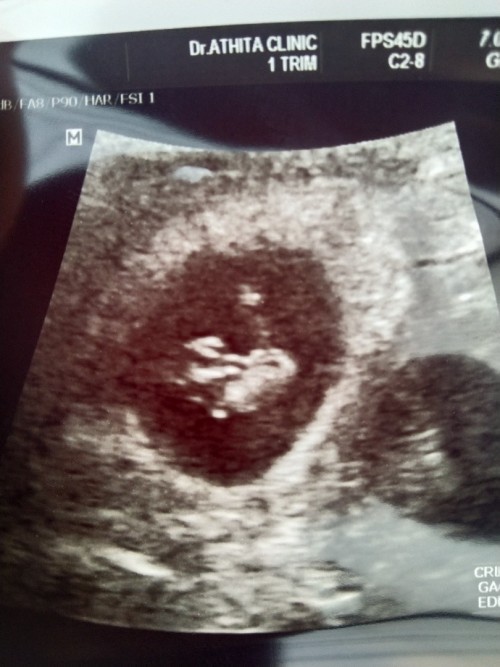

4 วีคกว่าๆเห็นถุงตั้งครรภ์ 6วีคเริ่มเห็นเป็นก้อนเล็กๆได้ยินเสียงหัวใจ 8 วีค น้องเป็นตัวดุกดิกๆค่ะ ตอนนี้11วีคกว่า รอซาวน์อีกทีตอน12วีคค่ะ .....ที่เห็นในรูปคือ8วีคค่ะแม่

อ่านเพิ่มเติมเพื่อนเรา 7-8-9 ไม่เจอตัว ท้องลมค่ะ ท้องพร้อมกัน เพื่อนเพิ่งแท้งไป เราเอง 6 สัปดาห์ เจอถุงตั้งครรภ์ เจอหัวใจตอน 6W 7-8W เห็นเป็นก้อนจิ๋วๆ 10W จะเห็นเป็นคนจิ๋ว แบบในรูปแล้วค่ะ